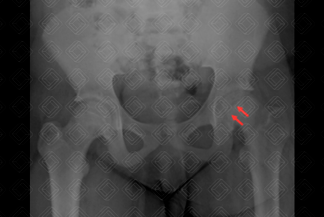

Texto alternativo para a imagem Figura 1. Créditos: Dra. Elazir Mota - Rio de Janeiro/RJ

Descrição da figura 1: Na radiografia de quadril na incidência anteroposterior (AP) observa-se discreto alargamento da fise no quadril esquerdo (setas vermelhas).

• Radiografia da bacia em AP e Lowenstein: A incidência em Lowenstein (ou posição da rã) é essencial nestes pacientes, por ser mais sensível na detecção das alterações iniciais do deslizamento epifisário. Por isso, deve ser rotina básica na avaliação radiológica dos adolescentes que se apresentem com claudicação ou dor no joelho/quadril. Observa-se que nestes pacienes acometidos, a epífise escorrega posterior e medialmente (figuras 1 e 2);